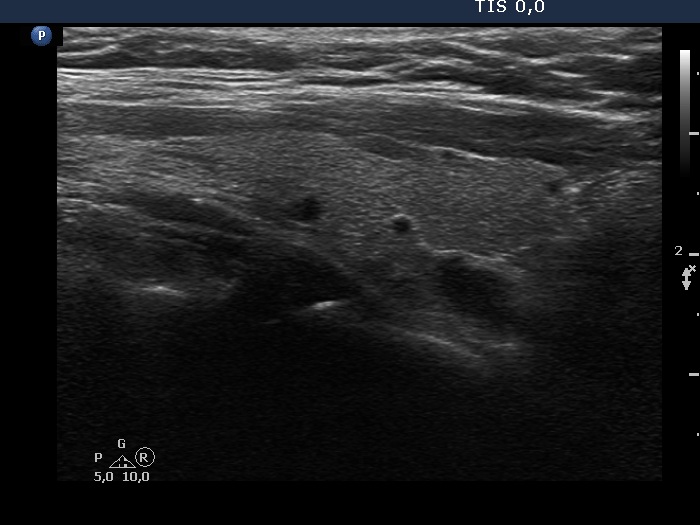

Ultrasonography. The thyroid was echonormal. There was a small cystic or deeply hypoechoic lesion in the lower-dorsal part of the right lobe. The lesion was not avascular. The left lobe has several discrete areas without any clinical or oncological significance.